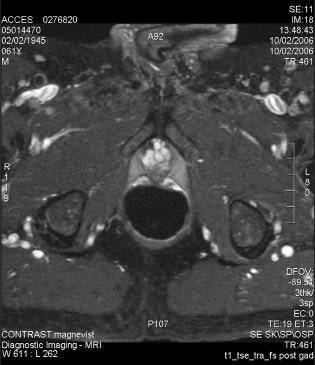

9) Retained “slough” that is preventing adequate bladder emptying can usually be resected or scraped out with a cold loop. The ultimate goal is that, after the sloughing of the ablated tissue, there will be a significant prostate defect as shown in the MRI images before and after HIFU treatment, Figure 5.

Figure 5. Pre-HIFU and Post-HIFU MRI images of the prostate.

MRI image of prostate before HIFU

Post-HIFU MRI showing cavity after prostate ablation and sloughing.